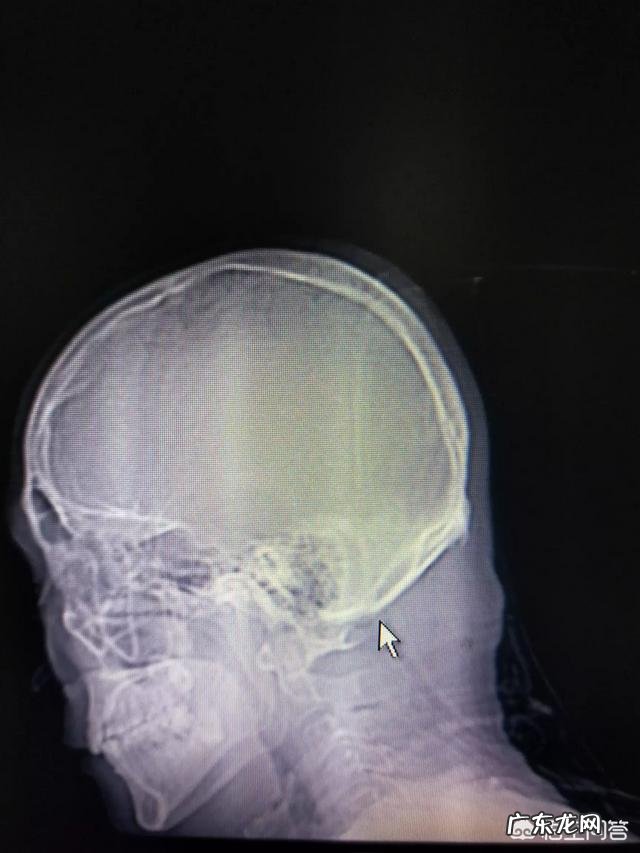

以上三图,图1.为环枕筋膜狭窄 。图2、图3为环枢关节挫位 。

二.椎动脉及交感神经型致病机理:我们1、2颈椎活动量最大,肌肉、筋膜慢性损伤,导致颈部肌肉力平衡失调,造成环枢关节挫位、环枕筋膜狭窄 。椎动脉从锁骨上动脉分出后顺颈椎横突孔进入颅内,上行段由于受横突孔保护不易受压迫,只有进入颅内段因环枢关节挫位或环枕筋膜狭窄而受压迫,又因交感神经结位于1、2颈椎故易受刺激,还有椎动脉上包绕交感神经 。故这两型基本同时存在 。其次枕大、小神经也易受压 。

2.大多数放射科及临床医生对这型颈椎病不了解,颈椎CT、MRl都不照上三个图片 。故而误诊率高 。